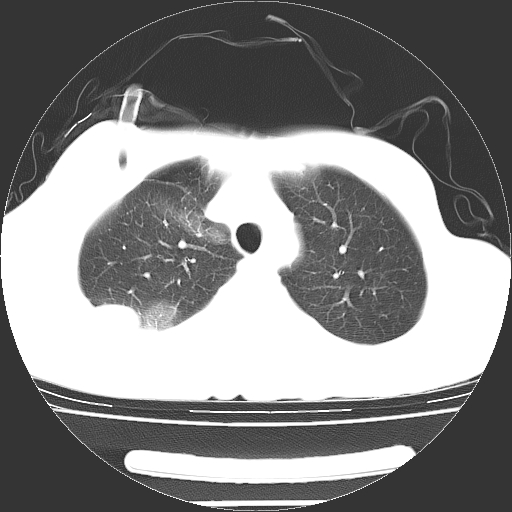

以下是引用dyqct在2008-4-29 8:43:00的发言:[br][br] 支持右侧胸腔包裹性积血。闭式引流管是不是插的太深了?

以下是引用zjzjr在2008-4-29 14:11:00的发言:[br]支持右侧胸腔包裹性积血。闭式引流管是不是插的太深了?胸腔引流,引流管快进入纵隔了.